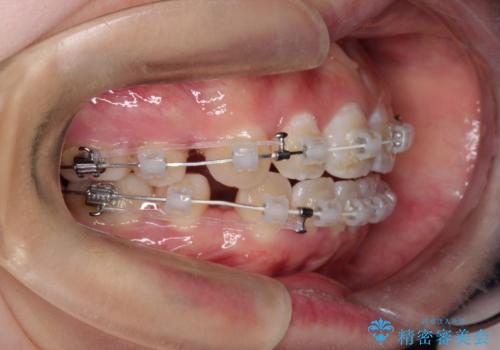

- 矯正装置

- 審美装置

- 治療計画

- ”口元を下げたい”が主訴で来院されました。

抜歯してワイヤー矯正を行い、口元も改善され大変満足していただきました。

小臼歯の抜歯を行うことで口元を改善することができました。